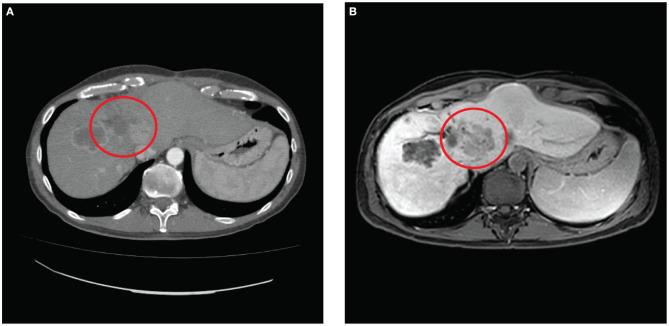

Cholangiocarcinoma (CCA) is the second most common primary tumor of the liver, and the recurrence after hepatic resection (HR), the only curative therapy, is linked with a worse prognosis. Systemic chemotherapy (SC) and liver loco-regional treatments, like trans-arterial chemoembolization (TACE) or radio embolization (TARE), have been employed for the treatment of unresectable intrahepatic metastasis (IM) with benefit on overall survival (OS), but SC has a limited effect on peritoneal metastasis (PM). In the last years, novel treatments like electrochemotherapy (ECT) with bleomycine (BLM) for IM and cytoreductive surgery with hyperthermic intraperitoneal chemotherapy (CRS and HIPEC) for PM have been applied in small series but with encouraging results. We hereby describe the first synchronous application of ECT and CRS and HIPEC for the treatment of a patient with IM and PM from CCA. A 47-year-old male patient with CCA underwent HR followed by adjuvant SC. After 14 months, for the occurrence of IM, the patient underwent a second HR and SC. Nonetheless, a new recurrence occurred and a third attempt of HR was proposed. Due to the intraoperative finding of unresectable IM with PM, no resective procedure was performed and the patient was referred to our center. CRS and HIPEC with cisplatin and mitomycin for PM and ECT with BLM on a bulky metastasis of the hepatic hilum were performed after 38 months from the first HR. The length of hospital stay was 19 days. At the computed tomography (CT) performed 11 days after treatment complete necrosis of the treated IM was detected. CT scan after 3 and 6 months and magnetic resonance after 9 months were performed. Necrosis of the treated IM nor PM but progression of the residual liver lesions was observed. After 3 months, the patient received SC and underwent TACE after 8 months and TARE after 9 months for the residual liver metastases. At 14 months from CRS and HIPEC, the patient is alive, in good condition, and with stability of the disease. The association of ECT and CRS and HIPEC could be safe and effective for the treatment of unresectable recurrent intrahepatic CCA with PM.

胆管癌(CCA)是肝脏第二常见的原发性肿瘤,肝切除(HR)作为唯一的根治性治疗方法,术后复发与预后较差相关。全身化疗(SC)以及肝局部区域治疗,如经动脉化疗栓塞术(TACE)或放射性栓塞术(TARE),已被用于治疗不可切除的肝内转移(IM),对总生存期(OS)有益,但SC对腹膜转移(PM)的疗效有限。近年来,新型治疗方法如用于IM的博来霉素(BLM)电化学疗法(ECT)以及用于PM的减瘤手术联合热灌注化疗(CRS和HIPEC)已在小样本中应用,但结果令人鼓舞。我们在此描述首例ECT与CRS及HIPEC同步应用于治疗一名患有CCA的IM和PM患者的情况。一名47岁的CCA男性患者接受了HR,随后进行辅助SC。14个月后,因出现IM,患者接受了第二次HR和SC。然而,又出现了新的复发,并提出进行第三次HR尝试。由于术中发现IM伴PM不可切除,未进行切除手术,患者被转诊至我们中心。在首次HR后的38个月,对PM进行了顺铂和丝裂霉素的CRS及HIPEC治疗,并对肝门部的一个巨大转移灶进行了BLM的ECT治疗。住院时间为19天。治疗后11天进行的计算机断层扫描(CT)显示,治疗的IM完全坏死。在3个月和6个月后进行了CT扫描,9个月后进行了磁共振检查。观察到治疗的IM和PM均无坏死,但残余肝脏病变进展。3个月后,患者接受了SC,8个月后进行了TACE,9个月后进行了TARE以治疗残余肝转移灶。在CRS和HIPEC后的14个月,患者存活,状况良好,疾病稳定。ECT与CRS及HIPEC联合应用对于治疗不可切除的复发性肝内CCA伴PM可能是安全有效的。